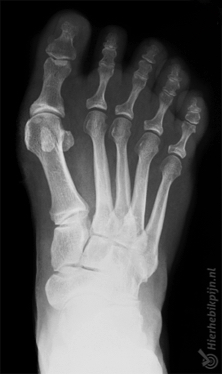

Hallux valgus Feilstilling av stortåen

Ved hallux valgus peker stortåen skrått innover mot de andre tærne. Mellomfotsbenet rett før stortåen har rotert feil vei (utover). Dette fører til en kul på utsiden av stortåen. Dette kalles en bunion.